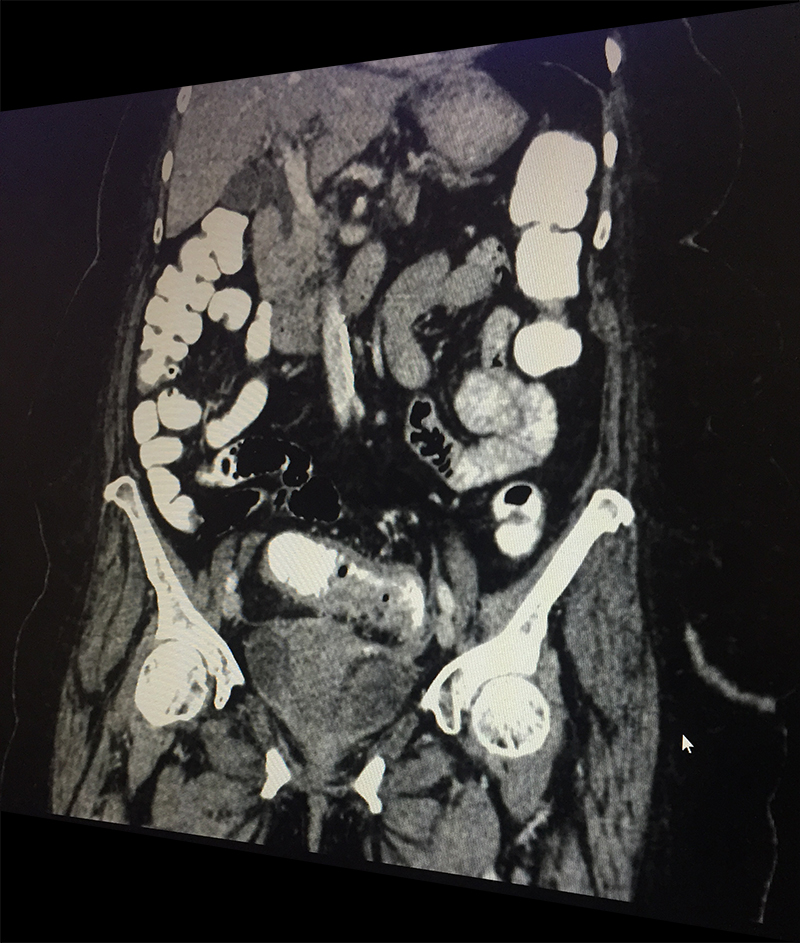

60 year old lady with an episode of sigmoid diverticular perforation with was managed with antibiotics and other supportive measures. A surgery was avoided at this time. She settled well, however started experiencing recurrent incapacitating abdominal pain due to sigmoid diverticular disease. A laparoscopic sigmoid colectomy and colorectal anastomosis was electively performed. She was discharged on postoperative day 5. She is now completely pain and symptom free.

Diverticula can develop in any part of large intestine. However they are most common in the sigmoid colon (part of large intestine just before rectum begins lying in the left lower abdomen). It is this area in which diverticula most often pose problems for the patients.

When a patient with acute abdominal pain is diagnosed (clinical suspicion) with a possible diverticulitis, he/she needs further investigations; blood & imaging study (CT scan of abdomen & pelvis) to confirm the diagnosis, rule out complications and plan the treatment based on the laid out guidelines. Most patients without complications & few with complications like contained perforation abscess are managed with antibiotics and occasionally with percutaneous drainage. Few patient require a laparoscopic lavage and drainage. Those with major perforation and fecal contamination require emergency surgery. It is done as an open procedure or by laparoscopic route depending on available expertise & patient condition. The involved sigmoid colon is resected and an end colostomy (bringing out the proximal end) is performed. The colon is reconstructed at a later date once patient has fully settled. If patient is too sick to tolerate a major surgery only a diverting colostomy (to bring the intestine lumen out on surface) is performed.